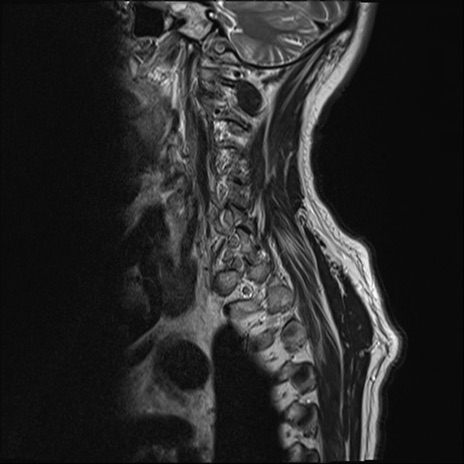

【整形】TIPS症例7 頚椎MRI T2WI(矢状断像)

頚椎MRI

T1WI(矢状断像)